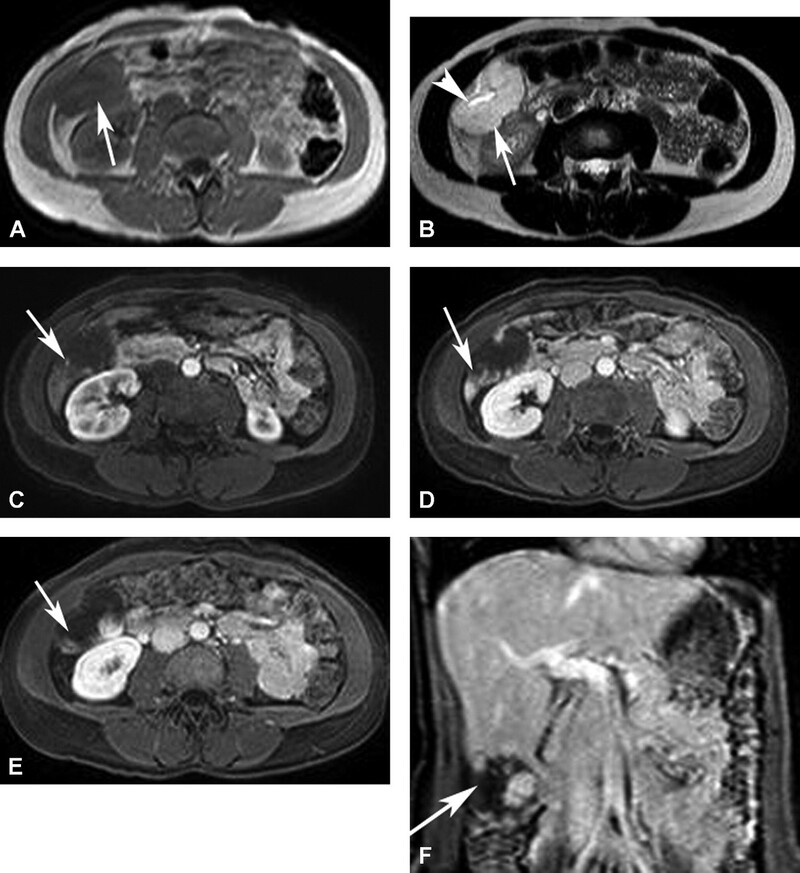

Hình 5. Hemangioma khổng lồ. Tổn thương giảm tín hiệu (mũi tên) trên hình T1W 3D GRE (A) và tăng tín hiệu (mũ I tên) kèm vùng nang ở trung tâm (đầu mũi tên) trên hình T2W SSFSE (B). Có bắt quang dạng nốt ngoại vi không kề nhau (mũi tên) ở thì ộng mạch (C), sau đó khuynh hướng lấp vào trung tâm hợp lưu (mũi tên) ở thì tĩnh mạch cửa (D). Tu y nhiên, không lấp đầy thuốc tương phản hoàn toàn (mũi tên ) ở thì muộn hình axial (E) và coronal (F).

FNH thường gặp nhất ở phụ nữ trẻ. Nguơi2 ta nghĩ rằng FNH là tổn thương hamartoma do dạng phát triển mất tổ chức hóa của tế bào gan và các ống mật hình thành một khối không có vỏ bao với ống mật và mạch máu có cấu trúc bất thường. Đặc điểm đặc trưng của FNH là hình thành sẹo xơ-mạch ở trung tâm. FNH thường nằm gân bề ặt gan. FNH có echo kém trên siêu âm. CT cản quang thấy bắt quang mạnh thì động mạch và tổn thương trở nên đồng đậm độ với nhu mô gan và khó phát hiện ở thì tĩnh mạch cửa. Sẹo trung tâm thường ít bắt quang ở thì động mạch sau đó bắt quang dần ở thì tĩnh mạch cửa và thì muộn (Hình 6).